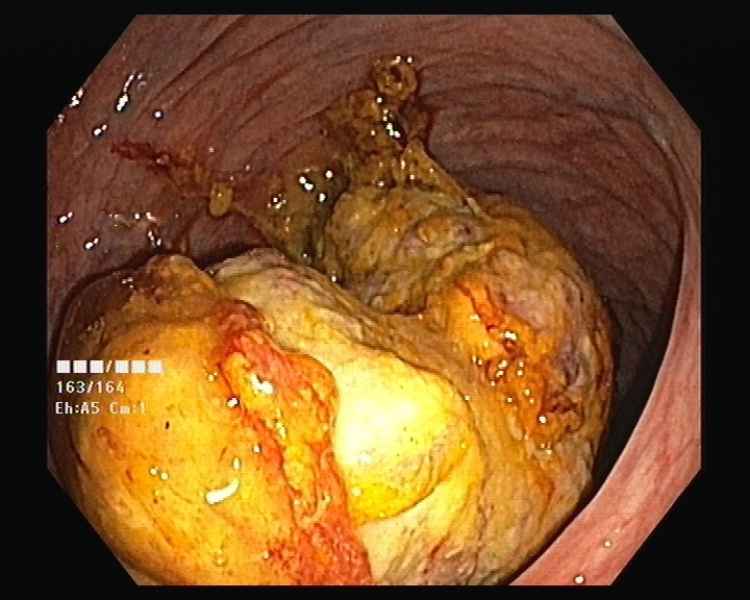

An unusual cause of upper gastrointestinal bleeding and small bowel obstruction

An unusual cause of upper gastrointestinal bleeding and small bowel obstruction

Maria Pia Costa Santos, Alexandre Ferreira, Vera Silveira, Luísa Glória, Marília Cravo

A 58-year-old black female, born in Angola, presented with melena, vomiting and a 7-year history of a right thigh mass that progressively increased in size. Her laboratory tests revealed iron deficiency anemia (hemoglobin 4.4g/dL). Computed tomography showed a large solid lesion in the right thigh, multiple smaller lesions in the lungs, pancreas and uterus, focal thickness of the small bowel wall and jejunal intussusception. Upper gastrointestinal endoscopy revealed multiple ulcerative lesions with elevated edges throughout the second and third portions of the duodenum, with 10-20 millimeters, without hemorrhagic stigmata. The histology of the duodenal and thigh lesions revealed a leiomyosarcoma.

An unusual cause of upper gastrointestinal bleeding and small bowel obstruction

Fotografia